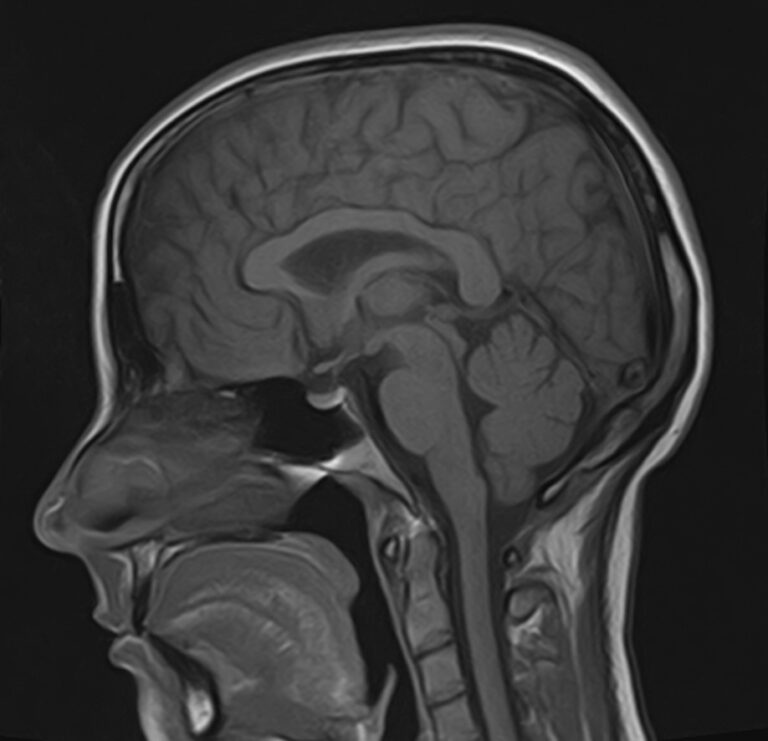

В нашей клинике мы проводим комплексное исследование, включающее МРТ головного мозга и всех отделов позвоночника. Методика комплексного обследования применяется при наличии у пациента сочетанных поражений головного мозга, спинного мозга и позвоночного столба.

Стандартная МРТ головного мозга дает важную информацию о состоянии и структуре мозговой ткани для выявления большого числа заболеваний, в том числе опухолевых образований, демиелинизирующих заболеваний, воспалительных процессов головного мозга и мозговых оболочек.

При подозрении на распространенный процесс с поражением различных уровней позвоночника целесообразно проведение МРТ для диагностики дегенеративно-дистрофических заболеваний, травматических, воспалительных изменений, а также опухолевых процессов позвоночника. Метод позволяет оценить состояние структур позвонков, позвоночного канала с расположенным в нем спинным мозгом и окружающих мягких тканей, кроме того, является основным способом диагностики демиелинизирующих заболеваний спинного мозга.

Исследование проводится на современном томографе TOSHIBA VANTAGE TITAN 1,5 Тесла. За счет высокой индукции магнитного поля аппарат обладает  высокой разрешающей способностью, что позволяет проводить точную диагностику заболеваний центральной нервной системы и позвоночника.